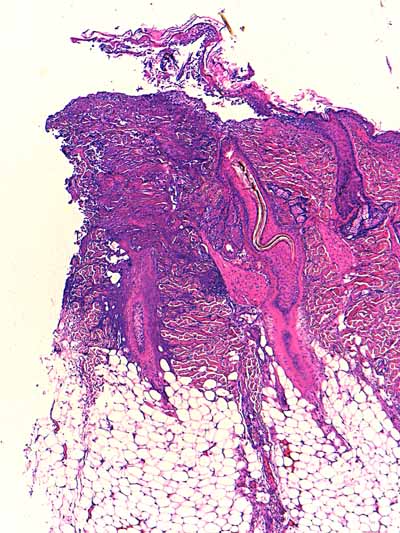

Photo 2 (Hémalun Eosine X 40) : biopsie réalisée en marge d’un ulcère.

L’épiderme, fragilisé, se détache artéfactuellement et se désolidarise du derme superficiel.

Le derme montre une plage cellulaire dense qui s’étend du derme superficiel jusqu’au derme profond.

En contact avec cette plage, se trouve un follicule pileux dont la tige pilaire est fragmentée

et circonvolutée dans son fourreau épithélial.

Légendes de la Photo 2 :

- Pointe de flèche orange : ulcère

- Ovale jaune : plage cellulaire inflammatoire s’étendant du derme superficiel au derme profond

- Flèche turquoise : follicule pileux dont la tige pilaire est fragmentée et circonvolutée dans son fourreau épithélial

- Flèches jaunes : épiderme fragilisé qui se détache du derme

- Double flèche orange : épaisseur épidermique

- Double flèche verte : épaisseur dermique

- Double flèche bleue : épaisseur hypodermique